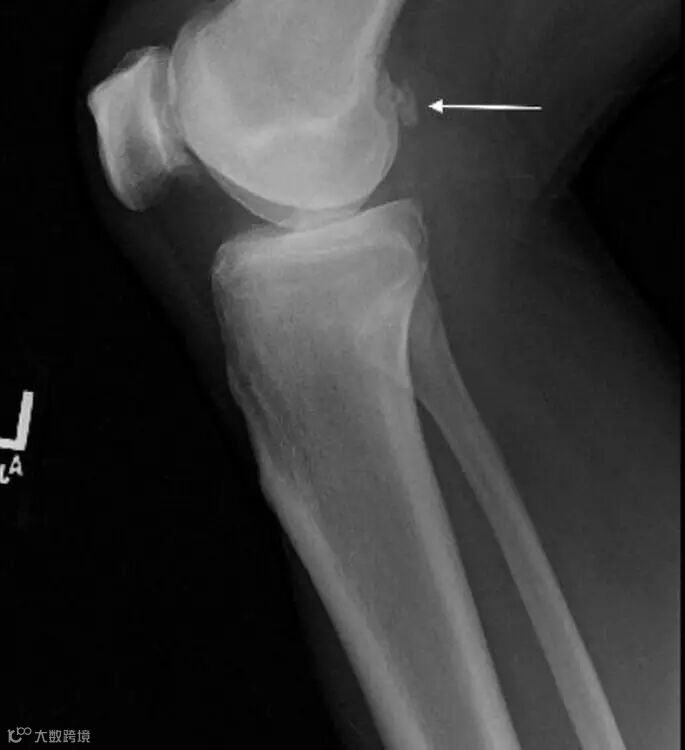

Lateral view of the left knee from two years prior shows the body positioned posterior to the femoral condyles (white arrow).